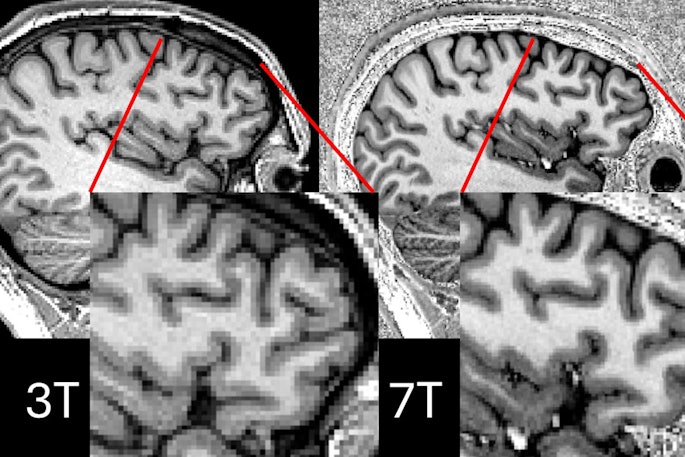

MRI identifies parts of the brain that remember words